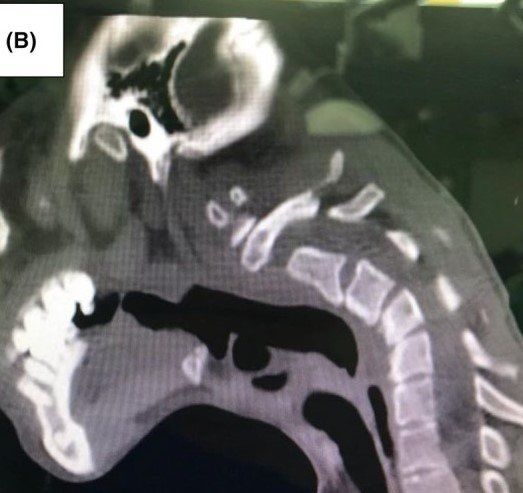

정밀 검사 결과, 경추 3~5번 부위에 휘어짐(후만측만)과 퇴행성 변화가 확인됐다. 의료진은 A씨에게 DHS 진단을 내렸다. 이는 주로 신경근육 질환에 의해 발생하는 희귀 증상이다.

(사진=PMC)